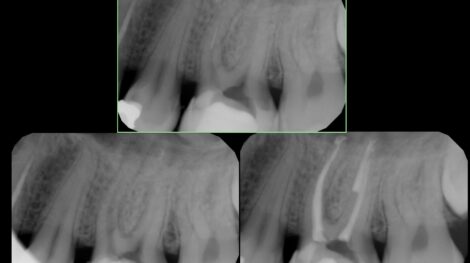

Usunięcie złamanego narzędzia i wyleczenie zmiany zapalnej